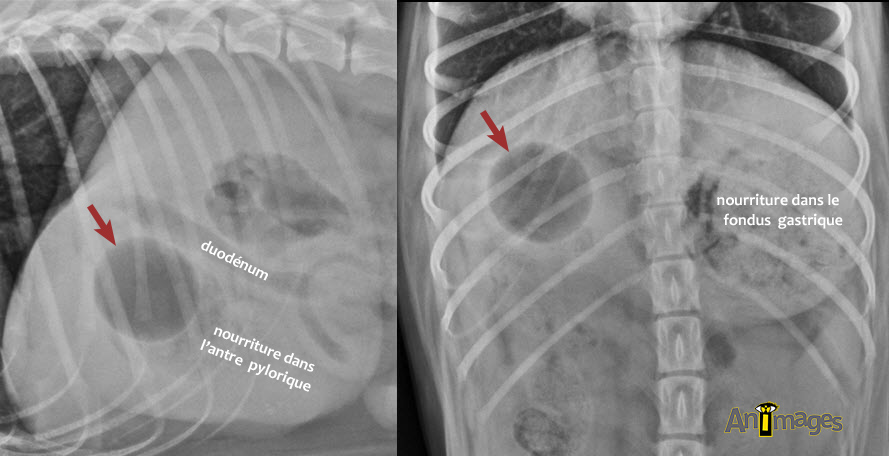

La visite de nombreux vétérinaires et TSA au kiosque pour se prononcer sur le petit quiz publié la semaine dernière nous a fait réalisé que nous n’étions pas les seuls passionnés du diagnostic radiographique ! La moitié des participants ont vu juste: ce chien avait mangé une petite balle de plastique remplie d’air qui se longeait dans l’antre pylorique, en compagnie de nourriture (cliquez sur l’image pour une vue plein écran). Remarquez la forme parfaitement circulaire et de taille identique sur les deux projections !